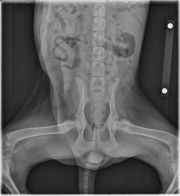

Today’s case is a 4.5-month-old female Husky cross with two-month history of fever and lameness. What is the significant radiographic finding?

VD Pelvis

There are radiolucent bands in the metaphyses of multiple long bones. The soft tissues surrounding the metaphyses are thickened, and there is periosteal reaction caudal to the left and right ulna.

Hypertrophic osteodystrophy